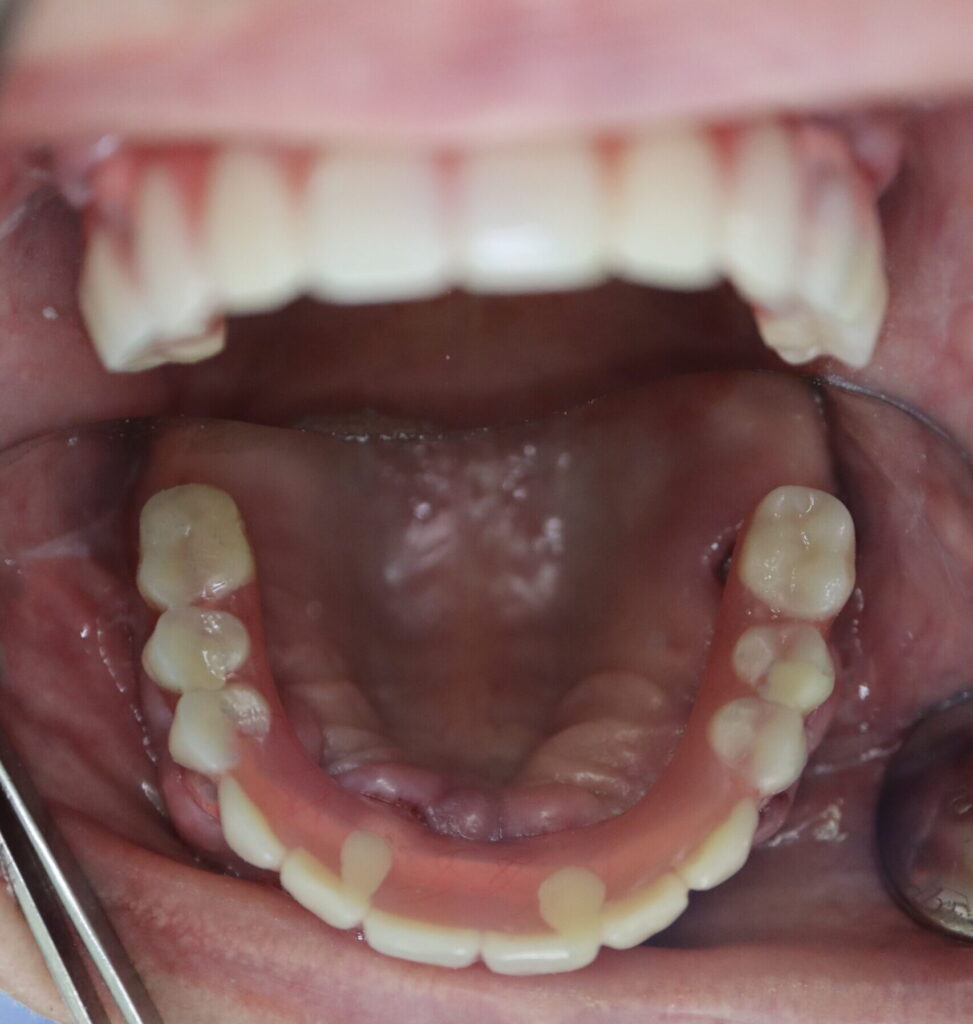

Ситуация до лечения

пациент до имплантации